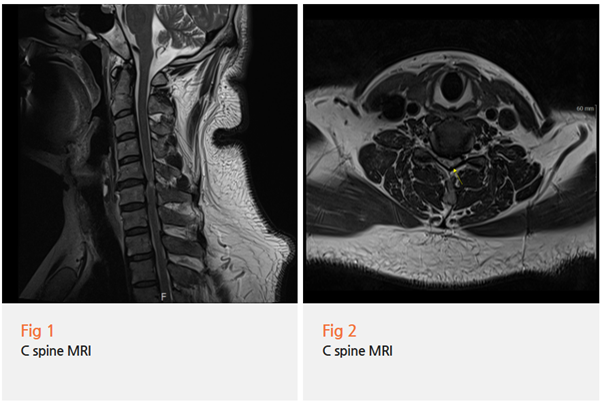

상황은 저도 예상했던 것보다 훨씬 심각했습니다.

단순한 목 디스크가 아니라

경추 협착이 상당히 진행되어 있었고,

더 충격적인 건

신경이 직접 손상되는 '경추 척수증'까지

진행된 상태였다는 거예요.